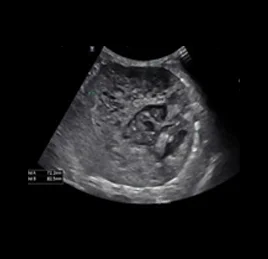

📍초음파 진단 케이스

• 지방간

• 담낭 점액종

• 비장 종양

• 수신증

• 만성 신부전

• 방광 결석

• 부신 종양

• 혈관 이상 - PSS

• 췌장염

• 췌장 농양

• 위장관염

• 소장 종양